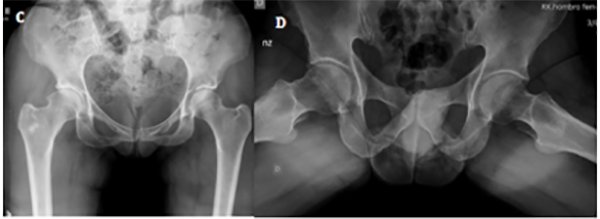

Se detectaron seis fallas (14.6%): dos casos progresaron a reemplazo total de cadera a los nueve y catorce meses postoperatorios (fig. 4), y cuatro presentaban síntomas persistentes luego de los nueve meses de la cirugía, los cuales, a la fecha, no requirieron de un procedimiento adicional.

Figura 4: Paciente femenina, cincuenta y siete años. A) Rx frente de ambas caderas, se observa esclerosis subcondral acentuada y signo de cross-over. B) Rx perfil de ambas caderas. Se visualiza el aplanamiento de la transición cabeza-cuello en ambos fémures. C) Rx ambas caderas, frente. Evolución a los tres meses postoperatorios. Se observa pinzamiento de la luz articular de cadera derecha. D) En la radiografía de perfil se constata una buena resección del CAM y del quiste de impacto en cabeza femoral, con progresión de la artrosis. E) Rx de ambas caderas, frente. A los seis meses de la cirugía se presenta a la consulta con coxartrosis polar superior. F) En el perfil se puede observar luz articular colapsada en el borde superoexterno de cadera derecha. G) Rx frente de ambas caderas. A los nueve meses de evolución se realizó la artroplastia total de cadera derecha.

En nuestro análisis, un caso de los que tuvieron que convertirse a prótesis se trató de una mujer de cincuenta y siete años, en el cual la luz articular comenzó a mostrar colapso a los tres meses. Debemos mencionar que en la radiografía preoperatoria se observan alteraciones de la forma y estructura compatibles con un grado 2 de la escala de Tönnis, sumado al hallazgo intraoperatorio de lesiones condrales grados 3 y 4, en acetábulo y fémur, respectivamente. Recientemente se ha reportado que un grado avanzado de artrosis y de lesiones condrales predispone a la falla. Esto está respaldado por distintos autores, quienes señalan que mientras más severas sean las lesiones, existen más posibilidades de precisar una artroplastia a mediano plazo.27–30